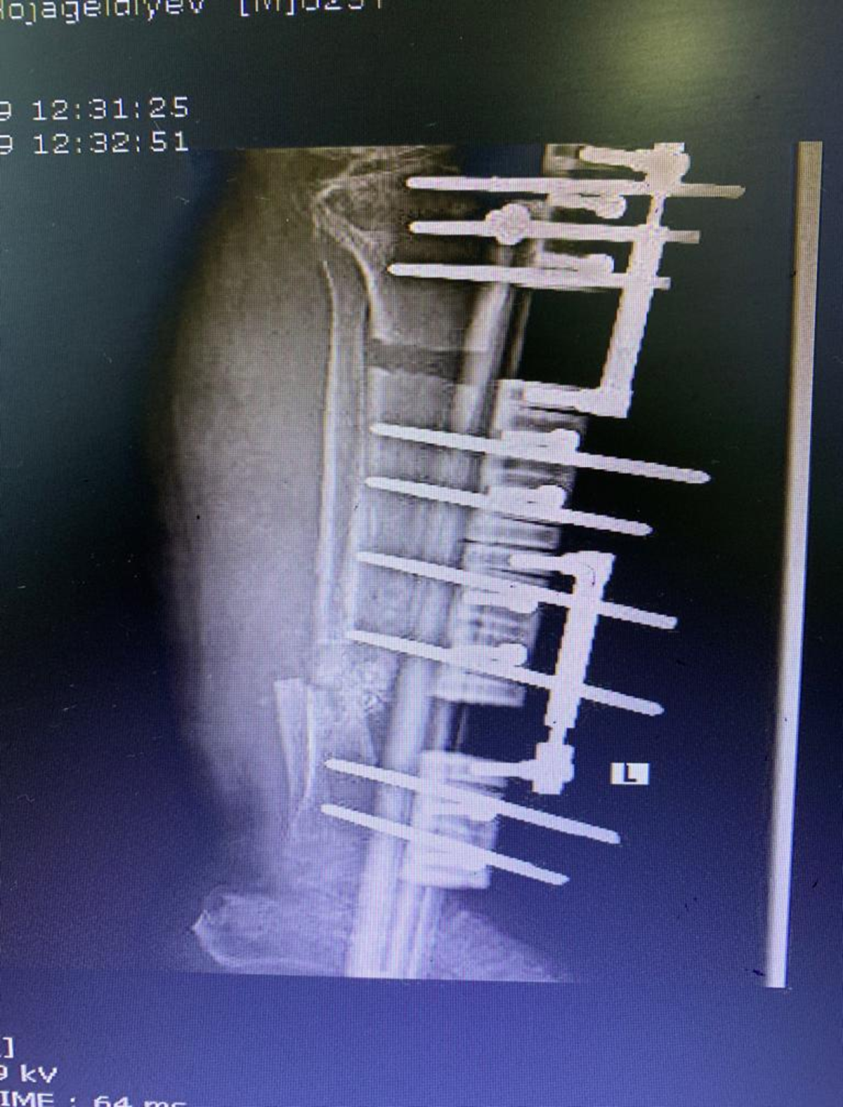

Another common scenario is one in which patient comes to us with open fracture of leg with an ununitied fracture with infection of bone and soft tissue previously elsewhere operated. In such cases the daunting task is to get rid of the infection and heal the fracture; here the technique of distraction osteogenesis (Ilizarov) comes to our rescue. First to get rid of the infection we get a pus culture done to assess the severity of infection and to assess the antibiotics that will be useful. During surgery we remove the dead and infected bone and soft tissues and bring the fracture ends together (docking), and apply the fixator (Monorail). Then we create a cut in the bone (corticotomy) and apply a distraction compression unit to help in creating a gap in the bone to allow distraction osteogenesis. Also antibiotic beads with the sensitive antibiotics are put at fracture site to kill the infection. Gradually over period of weeks the limb get lengthened to normal and infection is healed. The fracture also starts to heal by 3-4 months. The whole process might take upto 6 months.

Below are Xrays of one such case treated successfully by us over a period of 6 months.